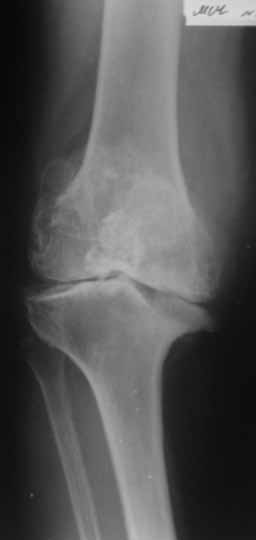

Пациентка 72 лет.Не обследовалась и не лечилась.

Работала поварихой до последнего времени. обратилась за медпомощью впервые. ходит без

дополнительной опоры. Основные жалобы на ограничение движений и боли в правом коленном

суставе. Финансовые возможности ограничены. Чем можно помочь? Артродез? Протезирование?